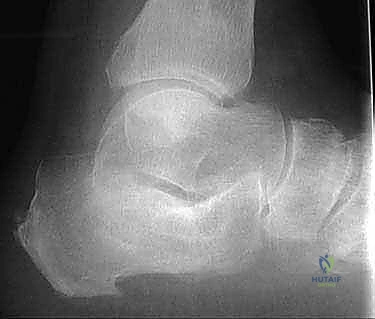

- الأشعة السينية (X-rays) متعددة الزوايا: لتقييم الانهيار العظمي وزوايا الكعب (مثل زاوية بوهلر وزاوية جيسان).

- الأشعة المقطعية ثلاثية الأبعاد (3D CT Scan): وهي الخطوة الذهبية والأهم في عيادة الدكتور هطيف. تتيح هذه الأشعة بناء نموذج ثلاثي الأبعاد دقيق للكعب المشوه، مما يسمح بتحديد أماكن الانحشار العظمي بدقة المليمتر، ومعرفة مدى تلف الأسطح المفصلية. بناءً على هذه الصور، يتم وضع خطة "القطع العظمي التصحيحي" قبل دخول غرفة العمليات.

- انحشار الأوتار (Tendon Impingement): بسبب توسع العظم للخارج، يضغط عظم الكعب على عظم الشظية (Fibula) والأوتار الشظوية المجاورة، مما يسبب ألماً حارقاً والتهاباً مزمناً في الأوتار.

يقوم الدكتور هطيف بإزالة الكتلة العظمية الزائدة التي تبرز من الجانب الخارجي للكعب. هذه الخطوة ضرورية جداً لتحرير الأوتار الشظوية (Peroneal Tendons) وتخفيف الضغط عن عظم الشظية، مما يقضي على الألم الجانبي ويسهل ارتداء الأحذية.